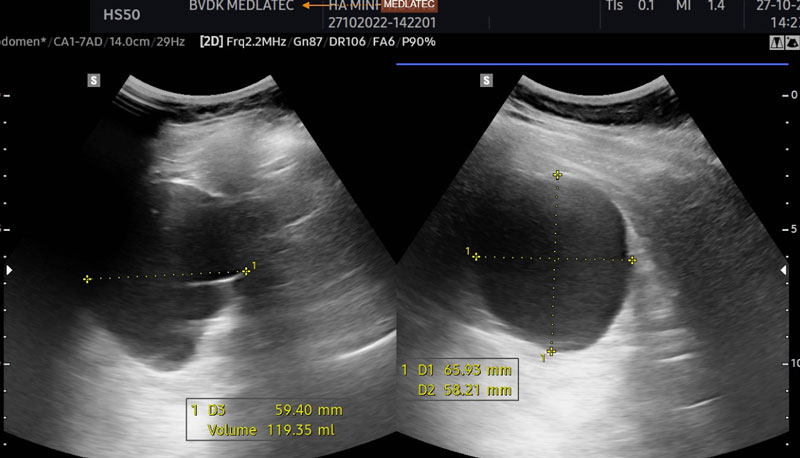

Hình ảnh nang thận khi siêu âm